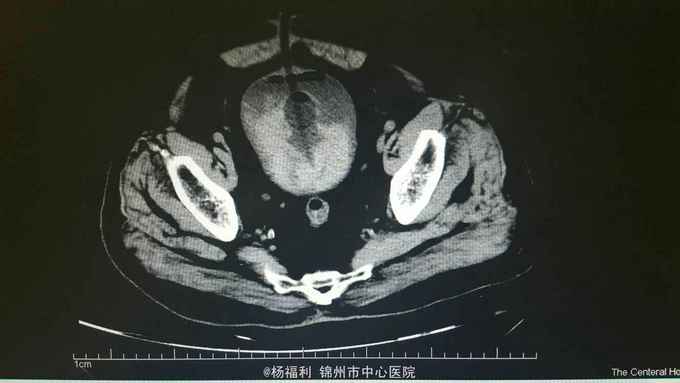

膀胱造瘘管内血尿伴血块,造瘘管周围窦口新鲜肉芽形成。耻骨上隆起,压痛阳性,扣诊浊音。 盆腔ct:见影像资料。内见大量血块。

尿潴留。膀胱内出血。膀胱造瘘术后。 给与患者留置尿管后行膀胱持续冲洗,血尿持续,于膀胱镜下给与患者清除膀胱内血块,发现造瘘口周围膀胱壁出血,滤泡样隆起,病理回报轻度不典型增生。电凝止血后回病房。